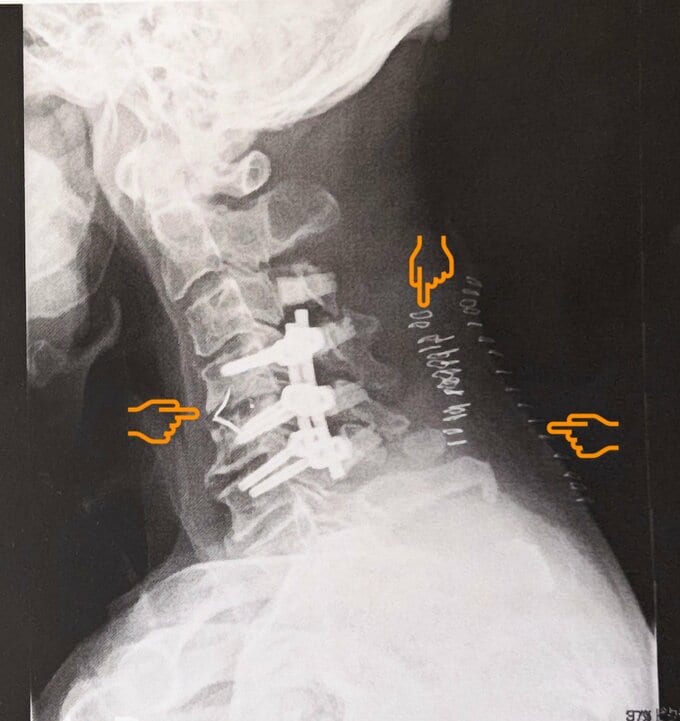

巨人さんは「昨日10日で頚椎術後.半年…こんなしんどい辛い半年に成るとは」と綴るとレントゲン写真をアップ。

投稿された画像では、巨人さんの首に複数のボルトが入っている様子が見て取れます。

最後に、巨人さんは「今 首には11個の人工物が」と、泣き顔の絵文字を添えて、その思いを綴っています。

そして、巨人さんは「首にボルトを6本入れる」「想定外の長時間の手術」「入院が予定より長く」と、当初の見込みより大幅に延びたことで、出演予定にも支障が出たことを関係者やファンに陳謝。次いで「術後 色々合併症が何ヵ所」「苦しんでおります 術前よりも数倍辛いです」と、綴っていました。